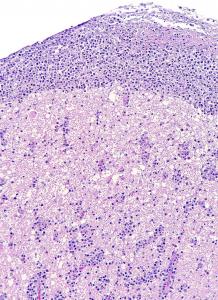

Este estudio, publicado en Transboundary and Emerging Diseases (2020; doi:10.1111/tbed.13713), ilustra el papel de la patología como herramienta de apoyo a los programas de conservación para especies en peligro de extinción. En este caso, la detección de dos herpesvirus presumiblemente nuevos en visones europeos se realizó a raíz del diagnóstico de un caso de linfoma principalmente neural/perineural con cuerpos de inclusión característicos de herpesvirus intralesionales en un visón europeo procedente del programa de cría en cautividad de esta especie amenazada. Estos virus podrían tener una influencia en el desarrollo de ésta y otras enfermedades que afectan a esta especie en cautividad y, por lo tanto, afectar a sus poblaciones.